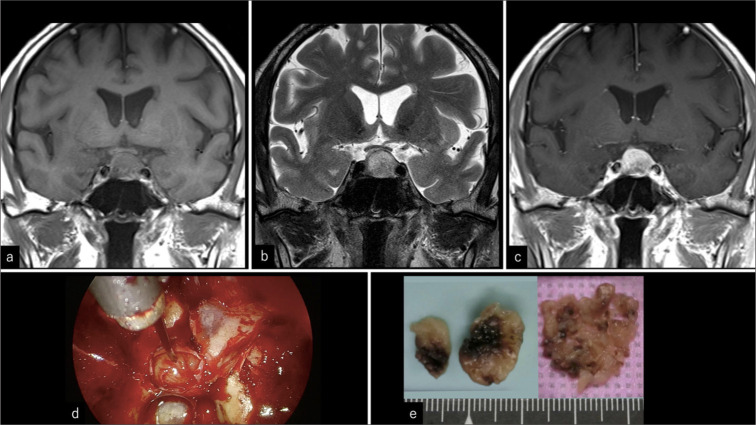

Most primary paragangliomas of the head and neck occur in the carotid, jugular body, tympanic ventricle, and vagus nerves. Primary sellar paragangliomas are rare, and their long-term outcomes remain unknown. It is also unclear whether they can be classified as asymptomatic incidentalomas in the sellar region. A 75-year-old man who had been followed up for 15 years for an asymptomatic non-functional pituitary adenoma strongly requested surgery and underwent endoscopic transsphenoidal surgery to remove the tumor. Intraoperatively, the tumor was found to be elastic, harder than the pituitary adenoma, fibrous, and not extremely vascularized. The tumor was excised extracapsularly, although residual tumor tissue remained in the medial part of the bilateral cavernous sinuses. A histopathological assessment revealed negative epithelial markers, positive neuroendocrine markers, and partial positivity for S-100, leading to a diagnosis of paraganglioma. Cervicothoracic and abdominal computed tomography, along with spinal magnetic resonance imaging, revealed no apparent neoplastic lesions. The patient experienced no recurrence for 5 years following the resection. The majority of sellar tumors are pituitary adenomas, craniopharyngiomas, Rathke's cleft cysts, or metastatic brain tumors. Herein, we present a case of an asymptomatic primary sellar paraganglioma that was successfully resected. The case highlights that paraganglioma can be included among incidentalomas in the sellar region. Routine follow-up should generally be recommended for patients with asymptomatic sellar incidentalomas.